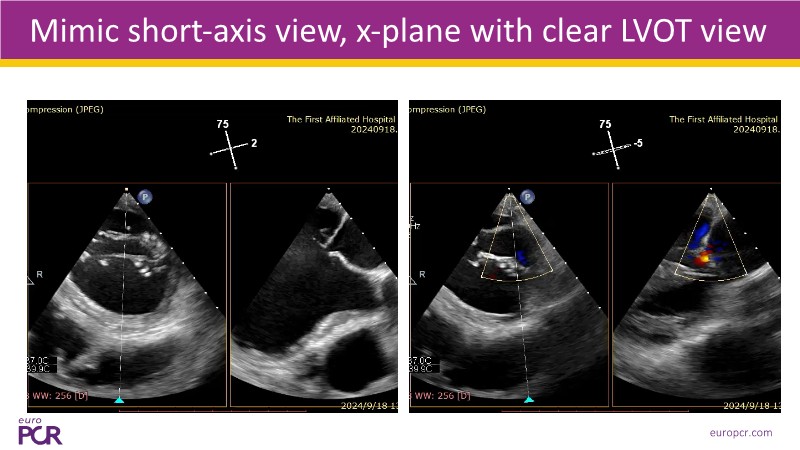

- To discover tips and techniques for mitral TEER in patients with challenging anatomy and difficult imaging